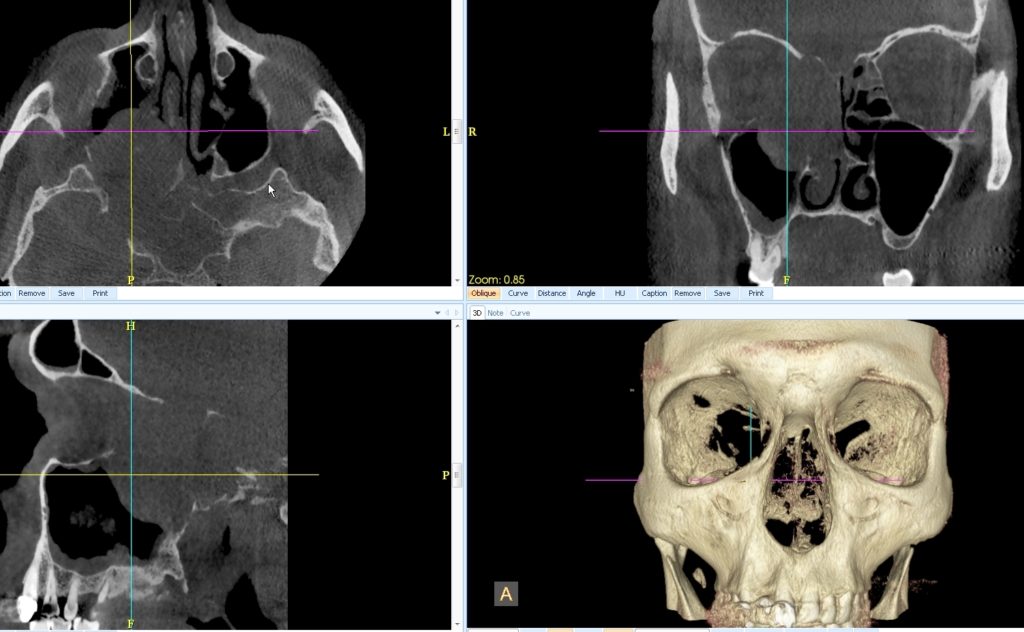

CONE BEAM :

1. Observez la formation tissulaire maxillaire et ethmoïdale droite centrée par la croix. Tentez de la décrire : masse

• Bien ou mal limitée ?

• Bordée par une capsule ou non ?

• Lysant les parois sinusiennes ou non ?

• Envahissant l’orbite droit ou non ?

• Occupant la fosse nasale droite ou non ?

• Homogène ou non ?

• Calcifiée ou non ?

1. Masse

• Bien limitée,

• Non bordée par une capsule,

• Lysant les parois sinusiennes maxillaires, ethmoïdales, ainsi que les parois orbitaires et nasales,

• Envahissant l’orbite droit,

• Occupant la fosse nasale droite,

• Homogène,

• Non calcifiée.